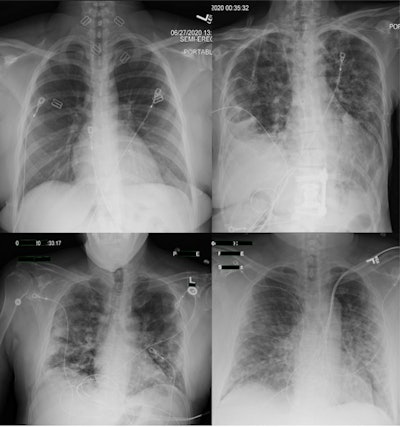

Chest x-rays may have had limited usefulness in diagnosing COVID-19 cases early in the pandemic, despite widespread use of the technology, according to a study published in the February issue of Clinical Imaging.

In a reader study, a group led by Dr. Judy Gichoya of Emory University in Atlanta evaluated radiologist performance in diagnosing COVID-19 on chest x-ray images acquired at the time patients presented in emergency departments. They found poor agreement among 10 readers from four academic institutions and that radiologist performance was ultimately nonspecific for diagnosing COVID-19.

The researchers culled RT-PCR results, clinical history, and chest x-rays of all patients tested between March 2020 and June 2020 across four academic medical centers. They included 984 RT-PCR-positive and 1,043 RT-PCR-negative radiographs. One hundred cases were read by all radiologists and 1,927 cases were read by two radiologists.

For 89 cases read by all readers, there was poor agreement for RT-PCR positive (Fleiss score 0.36) and negative (Fleiss score 0.46) exams, the researchers found. Agreement between two readers on 1,638 cases was 54.2% for RT-PCR-positive cases and 71.4% for negative cases.

Agreement was highest for RT-PCR-negative cases labeled as normal (50.4%, n = 479). In addition, reader performance did not improve with clinical history or time between chest x-ray and RT-PCR results, according to the findings.

"Emergency radiologists have nonspecific performance for interpreting COVID-19 on [chest x-ray] with a high rate of disagreement," the researchers stated.